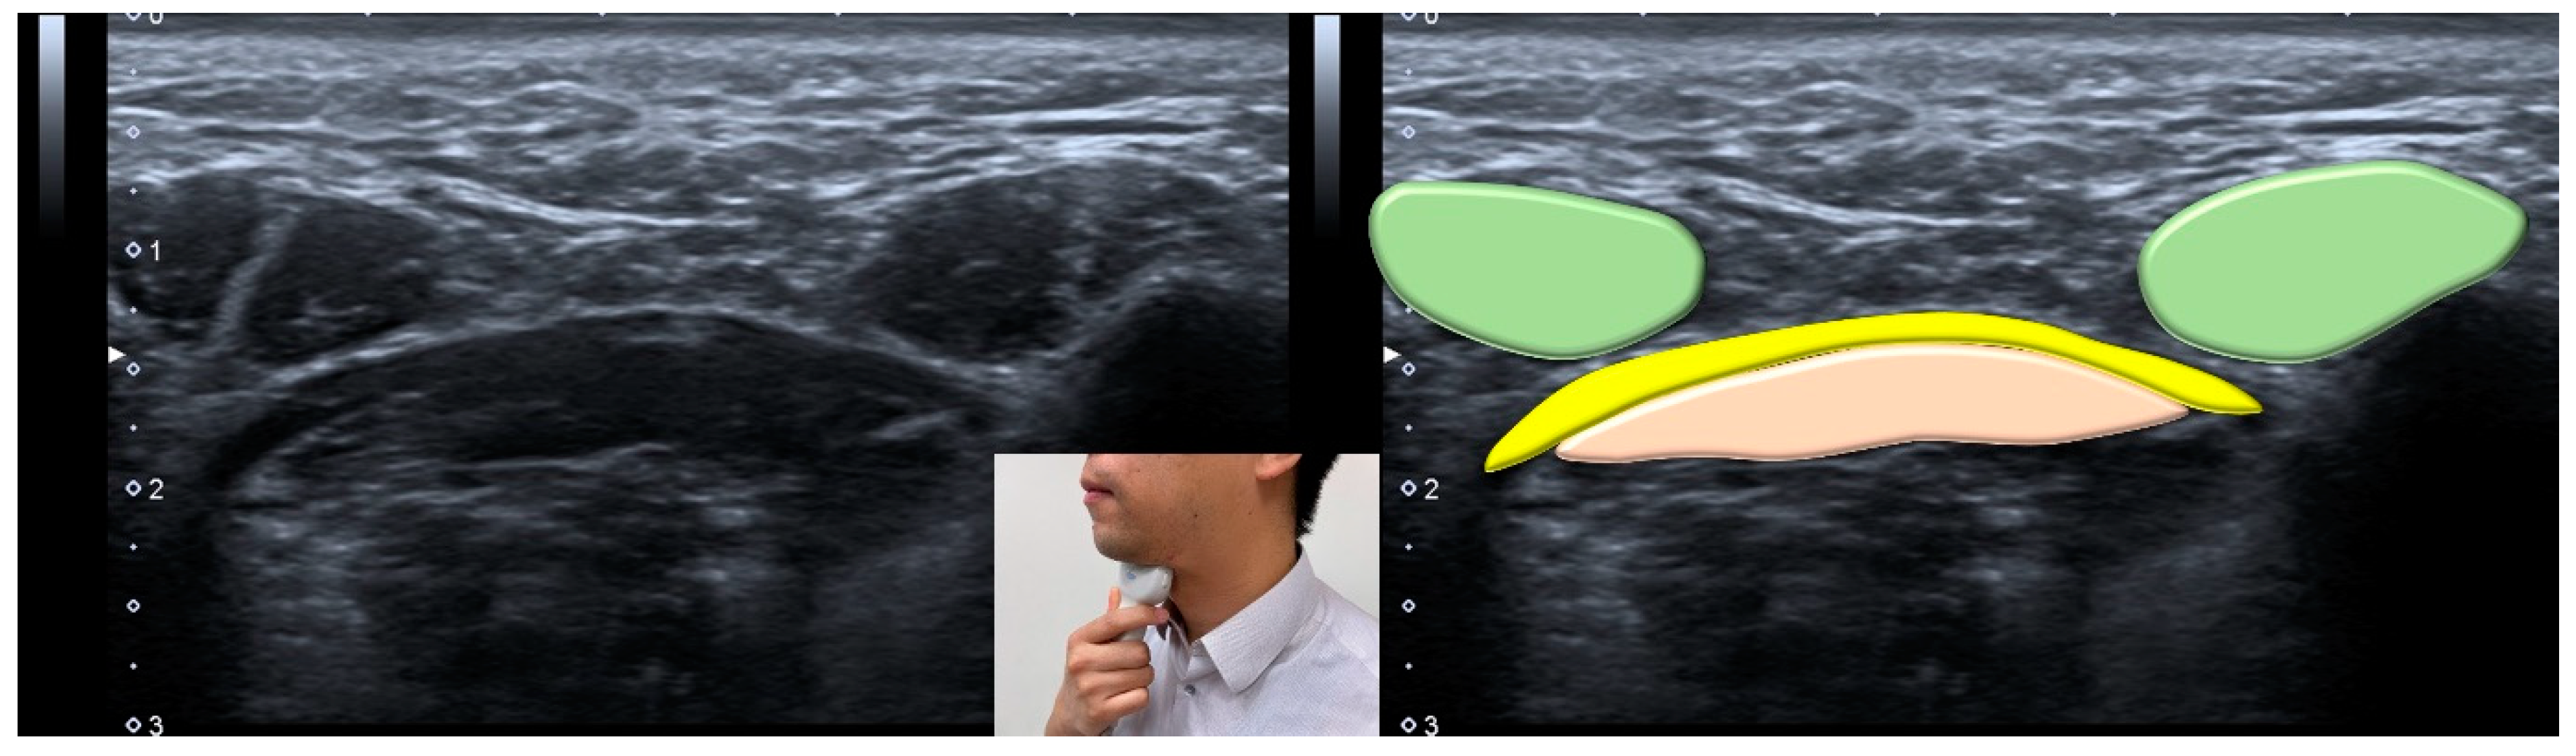

3.9. Ultrasonography

- Ogawa, N.; Mori, T.; Fujishima, I.; Wakabayashi, H.; Itoda, M.; Kunieda, K.; Shigematsu, T.; Nishioka, S.; Tohara, H.; Yamada, M.; et al. Ultrasonography to Measure Swallowing Muscle Mass and Quality in Older Patients With Sarcopenic Dysphagia. J. Am. Med. Dir. Assoc. 2018, 19, 516–522. [Google Scholar] [CrossRef]

- Gervasio, A.; D’Orta, G.; Mujahed, I.; Biasio, A. Sonographic anatomy of the neck: The suprahyoid region. J. Ultrasound 2011, 14, 130–135. [Google Scholar] [CrossRef]

- Ogawa, N.; Wakabayashi, H.; Mori, T.; Fujishima, I.; Oshima, F.; Itoda, M.; Kunieda, K.; Shigematsu, T.; Nishioka, S.; Tohara, H.; et al. Digastric muscle mass and intensity in older patients with sarcopenic dysphagia by ultrasonography. Geriatr. Gerontol. Int. 2021, 21, 14–19. [Google Scholar] [CrossRef] [PubMed]

| Ultrasonography | <1536 mm2 for the cross-sectional area of the tongue muscle <75.1 mm2 for the cross-sectional area of the digastric muscle |